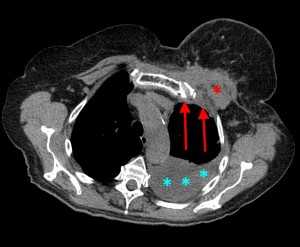

КТ: метастазы в легких при раке молочной железы. На изображении справа красной звездочкой отмечен опухолевый узел в молочной железе, красными стрелками - область прорастания опухоли в грудную стенку. Синими звездочками отмечен карциноматозный плеврит — скопление жидкости в плевральной полости. Слева стрелкой отмечен вторичный узел.